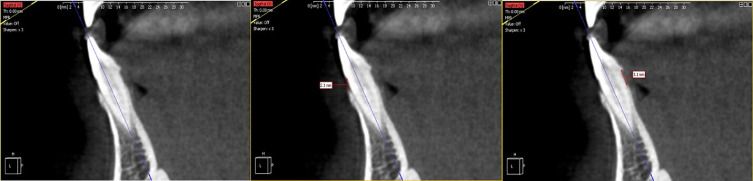

Results: The mean of the distance on buccal side for the central, lateral, and canine teeth were (1.6 mm), (1.6 mm), and (1.5 mm) respectively. On the lingual side, the mean for all teeth (central, lateral, and canine) was 1.7 mm. The study demonstrated a significant difference in distance across age groups (<30 and ≥30 years) for all teeth on both the buccal and lingual sides, except for the canine on the buccal side.

Conclusion: The distance from the CEJ to the bone crest on both the buccal and lingual sides varies significantly by age group. This data is essential for developing orthodontic, implant, and periodontal therapies.

Abstract Image